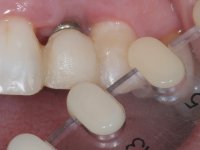

Treatment began with re-preparation of the cast post and core, with the purpose of placing the cervical finishing lines with an intra-sulcular location and simultaneously making a suitable temporary crown. With a very simple orthodontic treatment, the diastema was closed between the upper central incisors, and this position was stabilized with a wire placed on the palatal surface of the central, functioning as containment. Later, a slow orthodontic traction of tooth 2.2 was attempted, in order to reduce, although very slightly, the vertical bone loss in this area. At the end of the traction, tooth 2.2 was extracted and the area was provisionally rehabilitated with a composite resin crown bonded to the adjacent teeth. A dental implant was placed in the area of tooth 2.2 and the temporary crown was again bonded to resin, provisionally rehabilitating the patient during osseointegration. In tooth 1.3 a gingivectomy with an electric scalpel was performed, with the intention of raising the cervical level of 1.3 achieving greater harmony with tooth 2.3. Stabilized soft tissues were impressed using the open tray technique with putty and light addition silicones. Collection of the color of both the dental component and soft tissues was done by the ceramist in the office. In the laboratory, the impressions were transferred to plaster and gave origin to work models that were properly analyzed. It was decided to assemble a metal-ceramic abutment screwed onto the implant. This abutment was cast with a noble alloy and subsequently coated with coronary and gingival ceramics. Due to the inclination of the implant, the screwing inevitably conditioned the exit of the screw hole through the vestibular surface. In order to conceal this situation, the design of the abutment has already been conceived with the intention of accommodating on the vestibular surface the bonding of a feldspathic veneer. This abutment was tested in the mouth and adjustments were made in the gingival ceramic component. Its adaptation to the soft tissues was done in a subtractive way, with a drill, as well as additive, adding resin composed of gingival tonality.